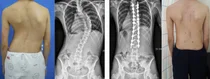

청소년기 척추측만증 환자에서 최소침습수술 우수성 입증

청소년 시기에 특별한 원인 없이 허리가 휘는 청소년기 특발성 척추측만증 환자에서 최소 절개를 이용한 ‘최소침습수술’의 우수성과 안정성이 입증됐다. 인제대학교 상계백병원 척추센터 장동균 교수팀과 고려대학교 구로병원...